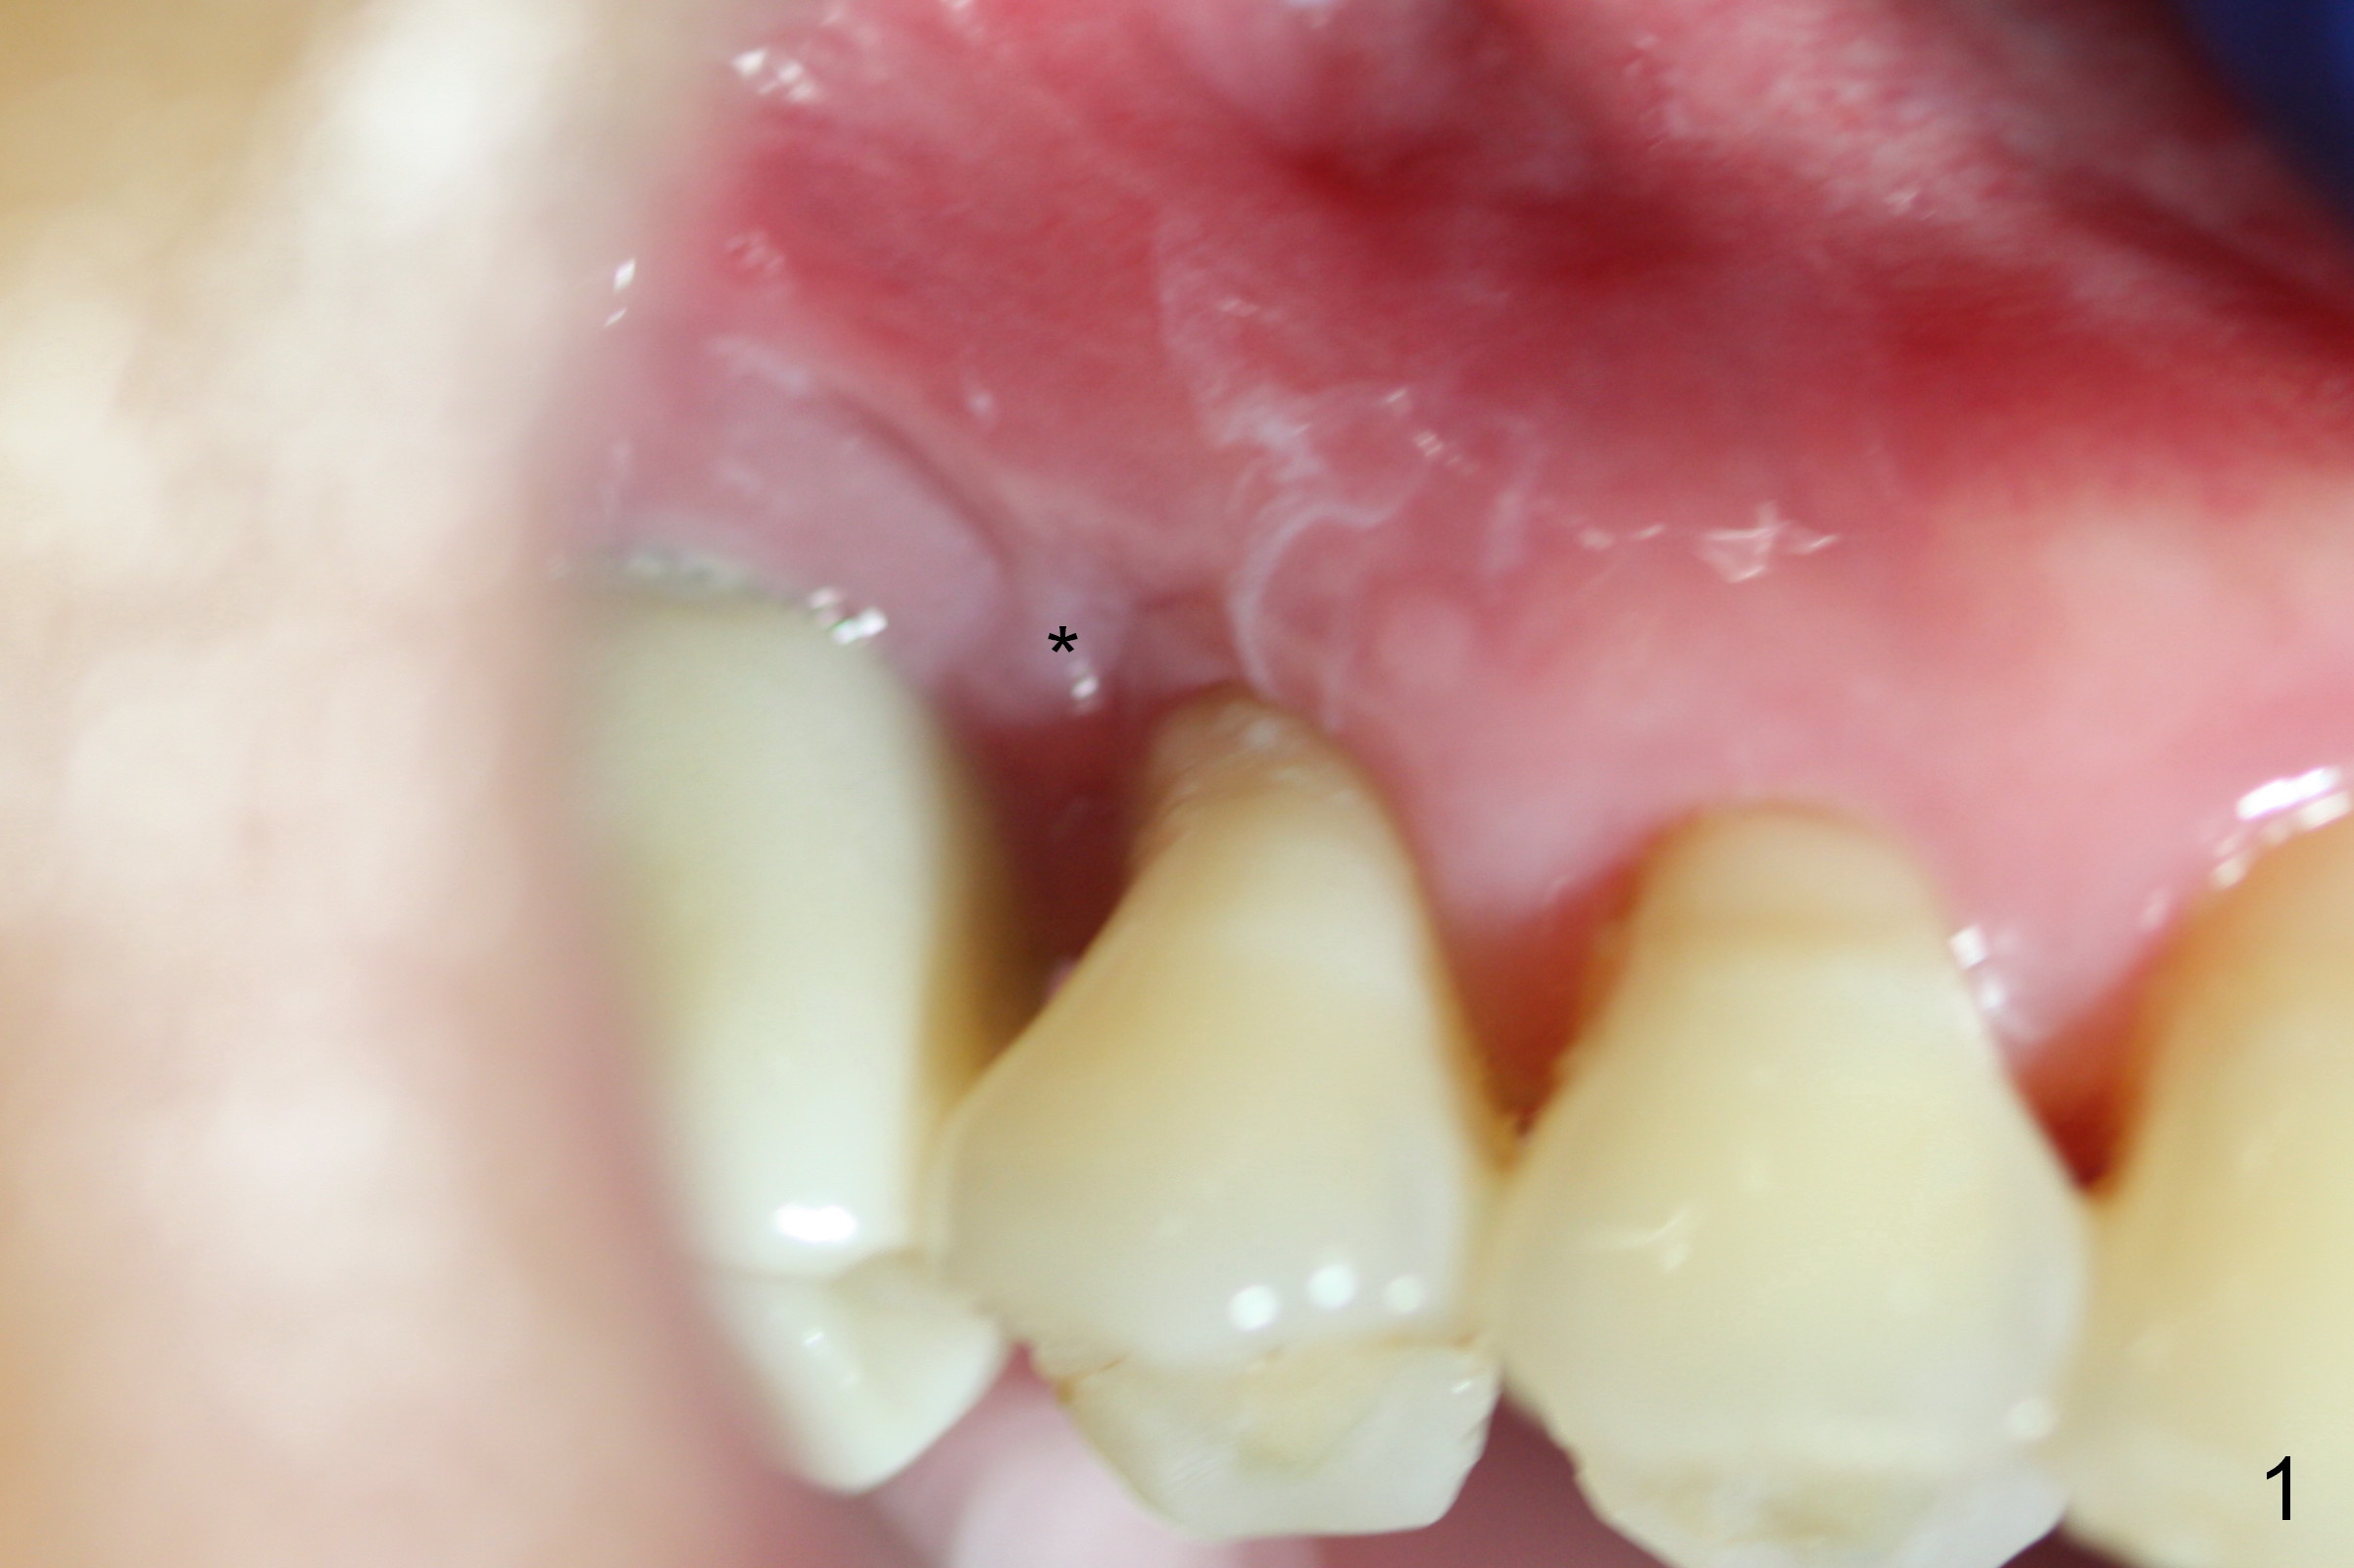

The distal buccal (Fig.1) and palatal (Fig.2) papillae (*) are recessive at the tooth #4. Following extraction and use of 3.8 mm Magic Drill, a 4.5x13 mm implant is placed lower than the mesial crest (Fig.3) to reduce the chance of the distal implant thread exposure. The latter is a measure to decrease peri-implantitis. A 4.5x5.7(4) mm pair abutment is placed (Fig.4,5). The remaining socket is filled with allograft/Osteogen placement. The large space between #3 and 4 implants is occupied by the healthy gingiva, where bone graft cannot get in.

The distal papilla reforms buccally (Fig.8 *) and palatally (Fig.9) 4 months postop. It appears that the 4 mm cuff of the pair abutment (Fig.10 >) is apical to the mesial crest (*). The distal coronal implant threads seem to be covered by bone graft (Fig.11 <). Therefore pair abutments with 5 mm or more cuff are required in cases of the uneven bone. Implants have to be placed deep. CT taken 3 months post cementation (10 months postop) shows that the implant is placed in the middle of the alveolus without apparent thread exposure. CT taken 1 year and 8 months post cementation (Fig.13) shows that the implant is placed in the middle of the alveolus without apparent thread exposure, as compared to those at #2 and 3, which are placed buccal (B).